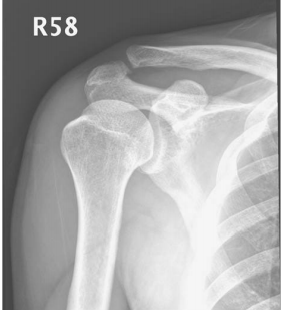

73.51歲男性病人,右側肩膀疼痛,且轉動受限。超音波及X光片檢查如圖,最可能的診斷為何? (A)旋轉環帶斷裂(rotator cuff tear) (B)退化性關節炎(degenerative arthritis) (C)肩峰及三角肌下滑膜炎(subacromial-subdeltoid bursitis) (D)鈣化性肌腱變性(calcific tendinosis)